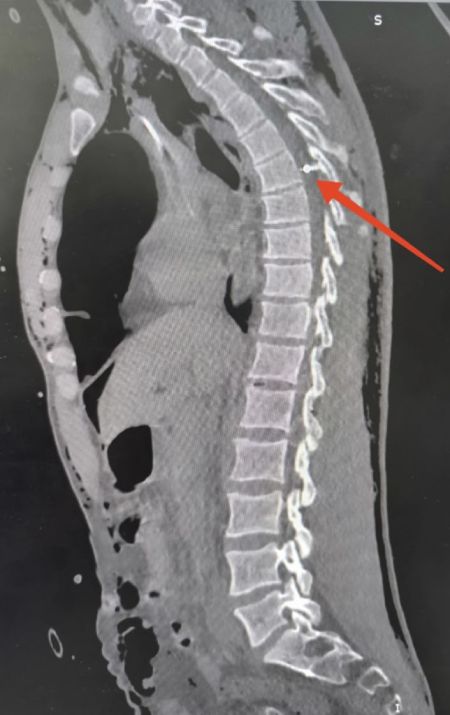

По словам Константина Эрдынеева, один такой крошечный шарик – всего 1-2 мм в диаметре – прошил военному позвоночник, спинной мозг и застрял в позвоночном канале. Врачи сделали декомпрессивную ламинэктомию.

- Работали с микроскопом, использовали интраоперационный рентген-контроль, магнит... Мы сделали всё, что возможно – и даже больше. Но этот проклятый шарик так и не нашёлся. Он спрятался где-то в спинном мозге, оставив после себя страшные разрушения, – пояснил нейрохирург. – Рана ушита, твёрдая мозговая оболочка восстановлена. Казалось, самый страшный этап позади, но в конце операции сердце бойца остановилось.